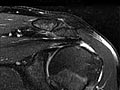

Magnetic resonance imaging (MRI) is a test done with a large machine that uses a magnetic field and pulses of radio wave energy to make pictures of the shoulder. Muscles, ligaments, cartilage, and other joint structures are best seen with an MRI. In many cases MRI gives information about structures in the body that can't be seen as well with an X-ray, ultrasound, or CT scan.

For an MRI test, you are placed inside the machine so that your shoulder is inside the strong magnetic field. MRI can find changes in the structure of organs or other tissues. It also can find tissue damage or disease, such as infection or a tumour. Pictures from an MRI scan are digital images that can be saved and stored on a computer for further study. The images also can be reviewed remotely, such as in a clinic or an operating room. Photographs or films of selected pictures can also be made.

Magnetic resonance imaging (MRI) of the shoulder

Normal:

The muscles, tendons, bones, and joints look normal in size, shape, and location.

No growths, such as tumours, are present.

No cartilage problems or tears, broken bones (fractures), or loose bodies are present.

No rotator cuff injury or tear is present.

No signs of inflammation or infection are present.

Abnormal:

A growth, such as a tumour, inflammation, or infection in the bone or joint, is present.

A collection of fluid is found, which could mean you have an infection.

Damage to ligaments, tendons, or cartilage is present.

Joint damage is present, and bones may show signs of disease or fracture.